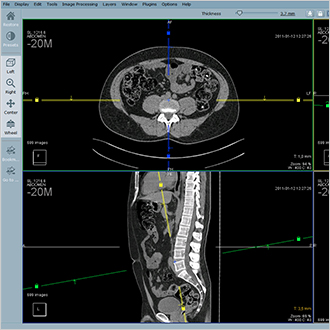

Hyper.PACS

HyperPACS is en universeel PACS voor alle medische beelden, zowel DICOM als non-DICOM. Het is gebaseerd op drie belangrijke pijlers: snelheid, stabiliteit en veiligheid.

Hyper.PACS biedt snelle toegang tot gegevens, stabiliteit en 100% gegevensbeveiliging.De interface is ontwikkeld in samenwerking met gebruikers voor intuïtieve diagnose, visualisatie en telegeneeskunde.

De workflow is geoptimaliseerd met hangende protocollen, weergave van de geschiedenis en parkeren van sessies. Aanvullende modules zoals orthopedische planning, beelduitwisseling telegeneeskunde zijn beschikbaar.